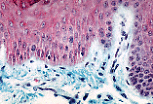

基底层的黑素细胞表现为细胞质淡染、细胞核深染的细胞。 | |

B型角化复层扁平上皮中,黑素细胞分泌黑色素并通过胞吐作用传递给邻近的角质形成细胞, 保护角质形成细胞及表皮下结构免受紫外线(U.V.)损伤。 | |

组织切片经丰塔纳银染法处理后,可在角质形成细胞和黑素细胞中均观察到黑色素。 | |

黑素细胞具有极长的指状突起,穿插于角质形成细胞之间,丰塔纳染色可显示这些突起。 | |

高倍镜下可分辨黑素细胞的突起(富含黑素小体),这些突起穿插在角质形成细胞之间(可通过细胞质内的张力丝识别角质形成细胞)。

角质形成细胞也含有通过胞吐作用从黑素细胞获得的黑素小体。 |

梅克尔细胞是位于基底层的淡染细胞。

可通过其凹陷的细胞核、以及下方真皮内 大量与之紧密相连的细小神经纤维 ,将其与黑素细胞区分;此外,梅克尔细胞在丰塔纳银染中呈阴性。 |

朗格汉斯细胞是抗原呈递树突状细胞,位于棘层。

常规染色的组织切片中无法与邻近角质形成细胞区分,但可通过特殊的组化技术(如本图的ATP酶染色)或免疫组化技术在光镜(M.O.)下检测到, 此时可显示其星状(树突状)形态。 |